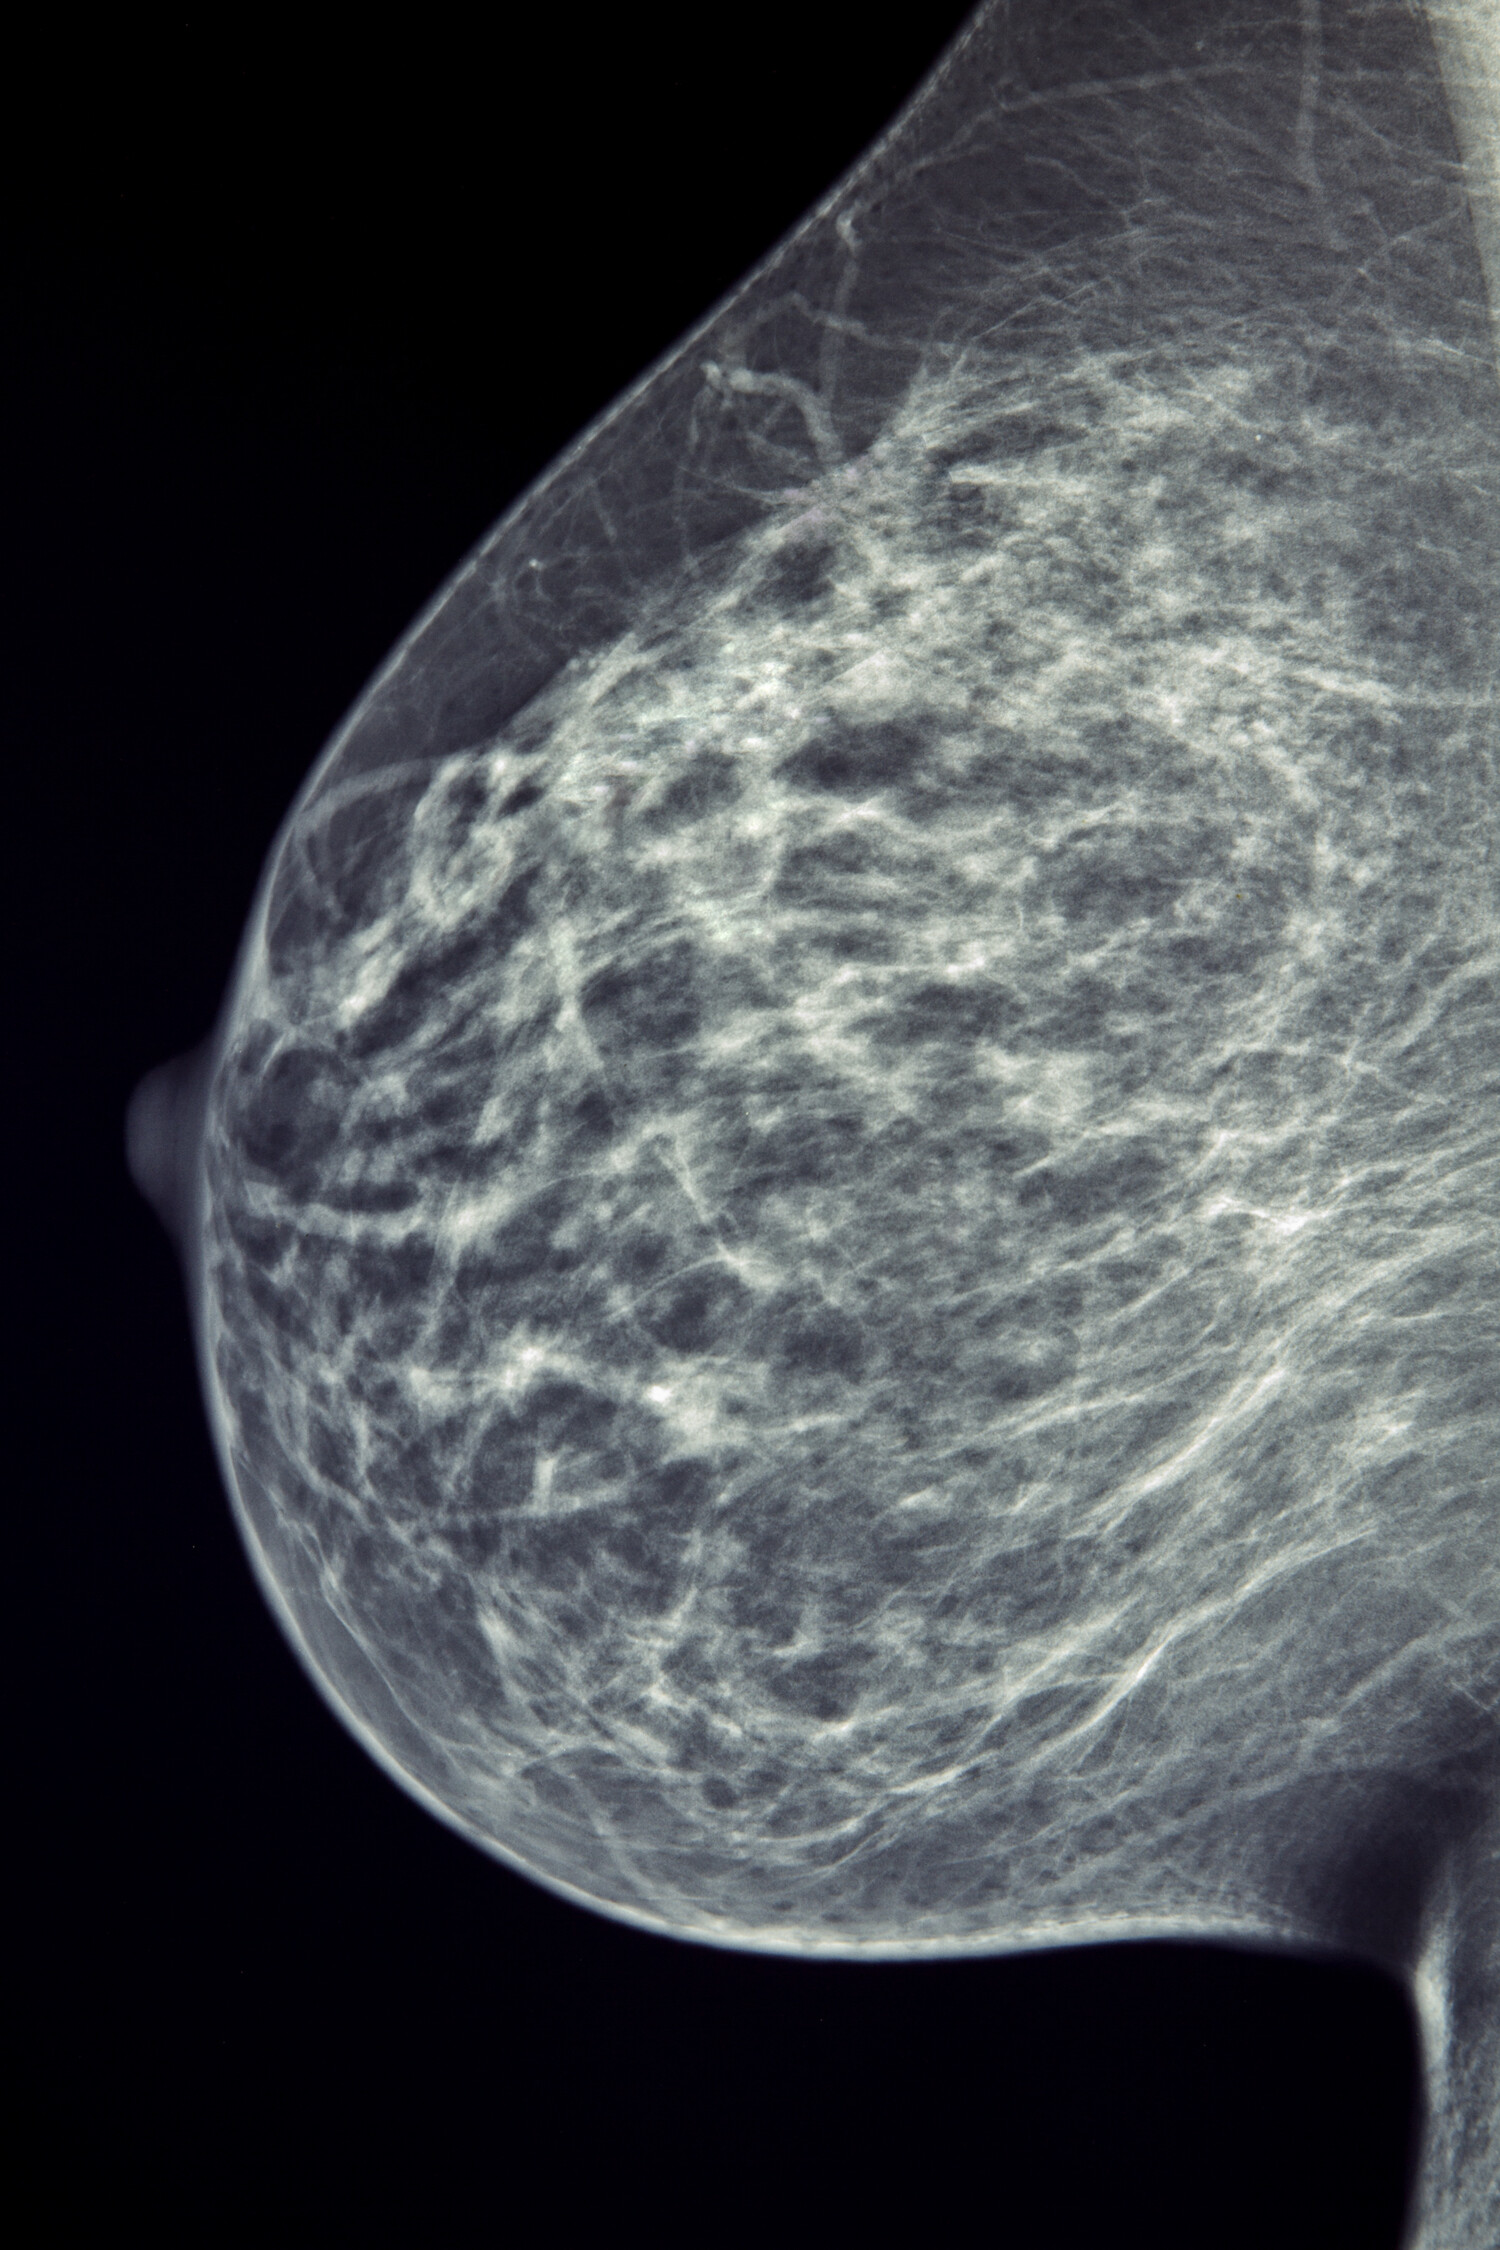

An example of a mammogram